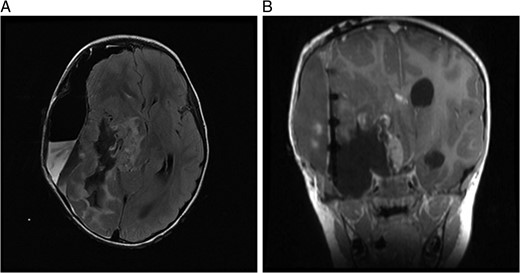

(A) MRI immediately following initial debulking of tumour showing a large subdural collection in a T2 FLAIR image and (B) coronal MRI post-op.

MRI 1 month post-op showed that the residual tumour in the basal ganglia, which extended inferiorly to the cerebellar pontine region had grown slightly larger. Also noted was a subdural fluid collection overlying the right cerebral hemisphere with extension into the interhemispheric fissure. Further debulking was carried out on the residual tumour. An MRI immediately post-op showed only 8mm of the tumour lying adjacent to the brainstem remained, which had previously measured 5.2 cm.

Postoperatively, the patient developed right-sided third cranial nerve palsy, left seventh cranial nerve palsy and a left hemiparesis. The deficits are likely attributed to a mild stroke following tumour resection. Further treatment, based on STUPP protocol, began 2 months post-op with a radical radiation therapy regimen and Temozolomide daily during treatment. She received a total dose of 55 Gy in 30 fractions over 6 weeks. She also received adjuvant Temozolomide 200 mg/m2 daily for 5 days in each of the six cycles. Delayed white cell count recovery between cycles prolonged the treatment course. Further surgical management of decompression of the tumour cyst was required in October 2014.